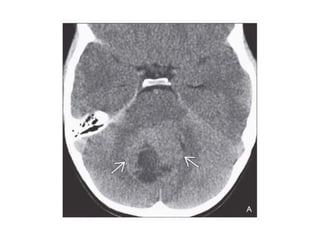

Left: axial NECT shows a poorly demarcated, infiltrative, mildly hyperdense

mass centered in pineal region with peripheral Ca++. There is invasion of

adjacent brain parenchyma & compressionof aqueduct of sylvius & resultant

hydrocephalus.Right: axial DWI MR shows restricted diffusion in solid mass &

better delineate the neoplasm & invasion of adjacent brain parenchyma.

Left: axial NECTshows a poorly demarcated, infiltrative, mildly hyperdense mass centered in pineal region with peripheral Ca++. There is invasion of adjacent brain parenchyma & compressionof aqueduct of sylvius & resultant hydrocephalus.Right: axial DWI MR shows restricted diffusion in solid mass & better delineate the neoplasm & invasion of adjacent brain parenchyma.